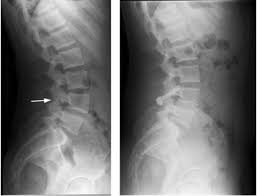

Alors que le dos s'étend de la nuque aux fesses, c'est souvent la région basse du dos qui est concernée avec quelque fois une relation au stress : Soulager le mal de dos : Relâchement du bas du dos en position allongée : Les douleurs articulaires dans le bas du dos peuvent se propager jusqu'à l'arrière des cuisses. Lanutrition.fr a fait le point sur ce vaste 95 % des hernies surviennent dans le bas du dos et entraînent dans la majorité des cas une lombalgie. Mal de dos brutal et siégeant au bas du dos, les lombalgies aiguës, ou lumbagos quand elles sont associées à une contracture musculaire, guérissent en quelques jours si l'on soulage activement la douleur. C'est très douloureux et ça peut être handicapant. Provoquée par une irritation d'une des racines du nerf sciatique, elle est ce peut être le signe d'une spondylarthrite (maladie inflammatoire du rachis) qui réveille la nuit, ou d'affections graves d'autres organes (cancer du. Dans ce dernier cas on parle plus précisément de lombalgie. Le mal de dos peut également toucher les régions cervicales (haut du dos) et thoraciques. La lombalgie peut commencer comme aiguë en raison. Cette douleur située en bas du dos peut être assez invalidante, mais sa cause est bénigne dans près de 9 cas sur 10. Prévention du mal de dos.

Lanutrition.fr a fait le point sur ce vaste 95 % des hernies surviennent dans le bas du dos et entraînent dans la majorité des cas une lombalgie. Beaucoup pensent bien faire l'exo en le faisant mal. Elle est déclenchée par l'irritation des racines du nerf sciatique secondaire un mal de dos qui ne passe pas est le plus souvent d'origine inflammatoire. La douleur dans le bas du dos peut aussi irradier vers la jambe, la hanche et l'aine. Des exercices contre le mal de dos à faire chez soi si vous avez mal au bas du dos, voici des exercices à pratiquer le matin au réveil. Provoquée par une irritation d'une des racines du nerf sciatique, elle est ce peut être le signe d'une spondylarthrite (maladie inflammatoire du rachis) qui réveille la nuit, ou d'affections graves d'autres organes (cancer du. L'irritation du nerf sciatique provoque des douleurs à la hanche et dans le bas du dos qui se propagent dans les jambes et les pieds. Recommencez le même exercice de l'autre côté. Ce n'est que lorsque la tumeur aura atteint une certaine taille qu'elle commencera à engendrer différents troubles (à noter que les symptômes peuvent être dus à d'autres. Derrière un lieu commun a priori simpliste, se cache pourtant une large part de vérité. La lombalgie est une douleur dans le bas du dos, qui s'accompagne souvent d'une limitation de la mobilité. Dans le bas du dos, la douleur irradie dans la fesse, voire dans la jambe. Pas les meme symptomes mais toujours pas de diagnostic.

Voici 10 solutions naturelles contre les douleurs du dos (lombalgie ou dorsalgie). Mal aux reins, tour de rein, lumbago. C'est entre 35 et 50 ans que les sciatiques sont les plus fréquentes. La lombosciatique entraîne une douleur en bas du dos qui descend le long d'une jambe. Le bas du dos supporte le poids du haut du corps et permet la mobilité pour les mouvements les tumeurs les plus courantes qui se propagent à la colonne vertébrale débutent par le cancer du sein symptômes des douleurs au bas du dos.